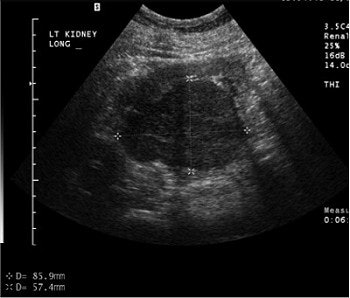

"Ultrasound with contrast has advanced over the years," Barr said. "We now have as many sequences ... as there are in MRI." At the time of these studies, the level of ultrasound technology that his group was using allowed them to inject contrast into a large renal cell carcinoma, and pick out the individual vessels in the cell. Also, the mass enhanced more than the normal renal cortex on ultrasound.

![]() |

A large renal cell carcinoma on pre-contrast ultrasound (above). After injection of the contrast agents (below), there is enhancement. Individual vessels in this renal cell carcinoma can be picked out; the mass also is enhancing more than the normal renal cortex. "If we increase the mechanical index, we can actually eliminate most of the parenchymal phase and actually look at discrete vessels," Barr said. Images courtesy of Dr. Richard Barr, Ph.D.

Part of the group’s sonographic technique is to increase the mechanical index, eliminate most of the parenchymal phase, and look at discrete vessels.